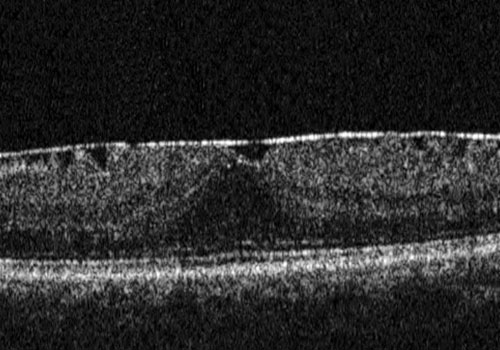

È una membrana fibrocellulare che si forma sulla superficie retinica interna per la proliferazione di cellule gliali migrate attraverso rotture della membrana limitante interna. Il risultato è rappresentato da un “raggrinzimento” della porzione centrale della retina, da cui deriva una distorsione delle immagini e un calo visivo, che può peggiorare nel tempo.

Nei casi più gravi la membrana tende a contrarsi e a stirare la superficie retinica. Il paziente inizia a lamentarsi di una visione distorta (metamorfopsia) e di un variabile grado di diminuzione dell'acuità visiva.

L’intervento di elezione è la vitrectomia con sistemi mini invasivi (25 o 27 gauge) e prevede il peeling della membrana epiretinica e della limitante interna.